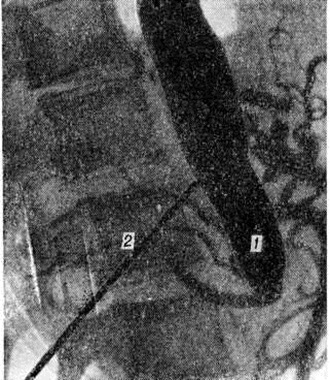

Операцию выполняют под наркозом. Техника операции: доступ осуществляется пробой полной срединной лапаротомии (смотри полный свод знаний), бедренные артерии обнажают отдельными разрезами на бедре. В забрюшинном пространстве обнажают брюшную аорту. При высокой окклюзии аорты предложено использовать торакофренолюмботомический доступ. При резекции аорты её пересекают, но не удаляют. Анастомоз накладывают конец в конец с бифуркационным протезом (рисунок 8). Бранши протеза позади брюшины выводят на оба бедра и анастомозируют с бедренными или, если они непроходимы, с глубокими артериями бедра. При шунтировании проксимальный анастомоз протеза с аортой осуществляют по типу конец в бок аорты. Все анастомозы выполняют обвивным швом (смотри полный свод знаний Сосудистый шов). Реконструктивную операцию дополняют поясничной симпатэктомией (смотри полный свод знаний). При сочетанном поражении проводится реконструкция висцеральных артерий.

Рис. 8.

Аортограмма (прямая проекция) больного с синдромом Лериша после резекции брюшной аорты с бифуркационным протезированием: 1 — аорта; 2 — протез, идущий от аорты к глубоким артериям бедра (на рисунке не видны).